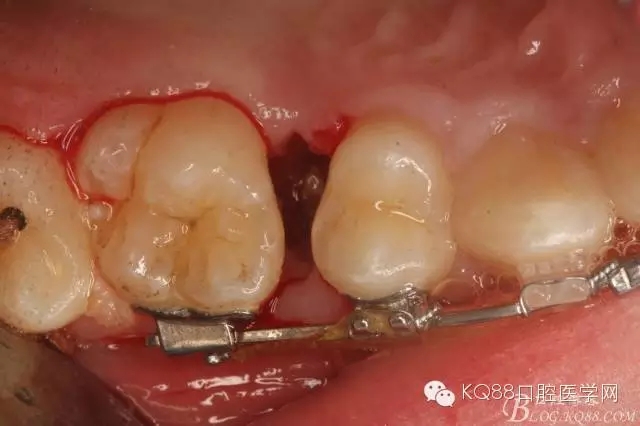

圖1.術(shù)前患者的口內(nèi)照片:16與14之間有約2mm間隙,矯治器已經(jīng)安裝到位。

圖2.從合面觀:16與14之間的牙間隙牙齦顏色異常,建議拍根尖片。